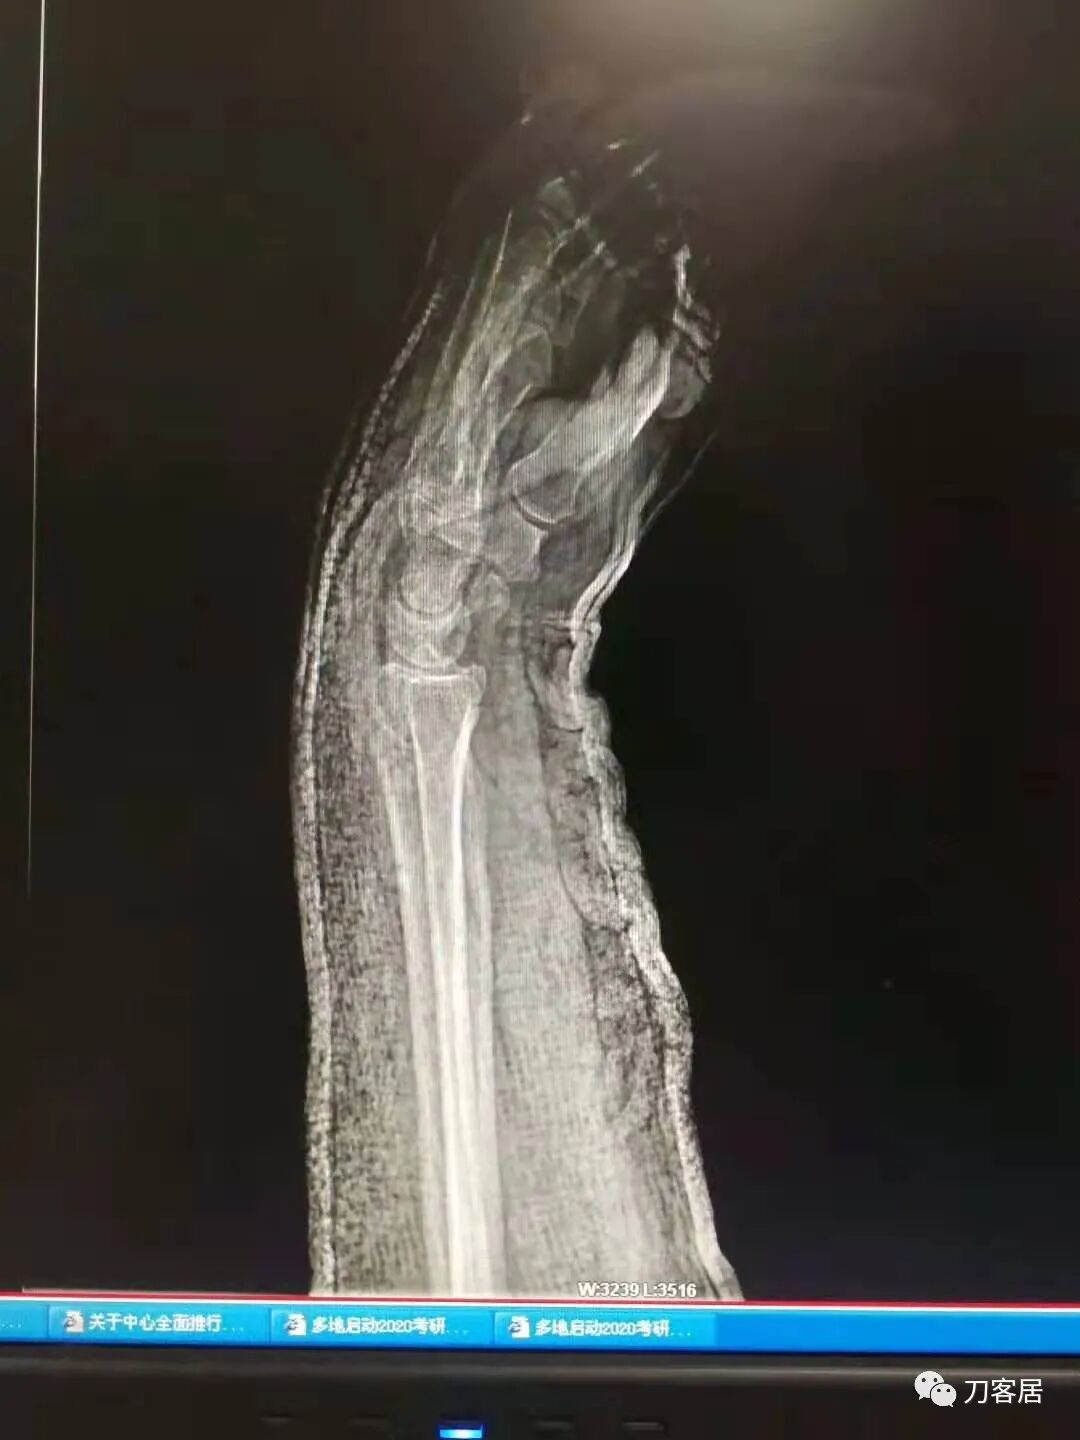

2021年7月21日,在中华骨科网儿童骨科病例讨论群里,看到了几张图片,是某仁慈医院的一位手外科医生做的手术,被某地器械厂家发在朋友圈里炫耀,有小儿骨科医生看不过去,就发群里请大家评论,引起众多小儿骨科医生的批评。

下面是这个6岁孩子,尺桡骨远端双骨折的术前及术后片子和外观照片。

1.  这是一个很简单的6岁儿童无移位的尺桡骨远端骨折。没有皮肤损伤,没有移位,没有骨折碎块儿。

2.  这个骨折处理起来也很简单,单纯的打石膏托或者中医的小夹板,或者正规的包括腕关节和肘关节的管型石膏外固定4周即可治愈该骨折。实在不行,如果这个孩子比较听话,不太调皮的话,用一本书,一个三角巾悬吊固定4周,都可以治愈该骨折。但是给这个患者用外固定架做了手术,而且桡骨远端的几颗克氏针距离骨折线太近,其中一枚克氏针进入到骨折间隙内。从这个术中图片来看,术者的外固定手术技术也有待于进一步的提高。毕竟术者应该还很年轻。从X线片来看,前臂及手的尺侧有不透光影,应该还使用了外固定石膏绷带托,而且我猜测应该是高分子的石膏绷带托,这个是纯属猜测,不一定是对的,不过如何解释前臂尺侧的不透光影呢?如果真是用了石膏绷带外固定的话,那为啥要做手术呢?外固定架术后就不该再用石膏绷带托辅助了。